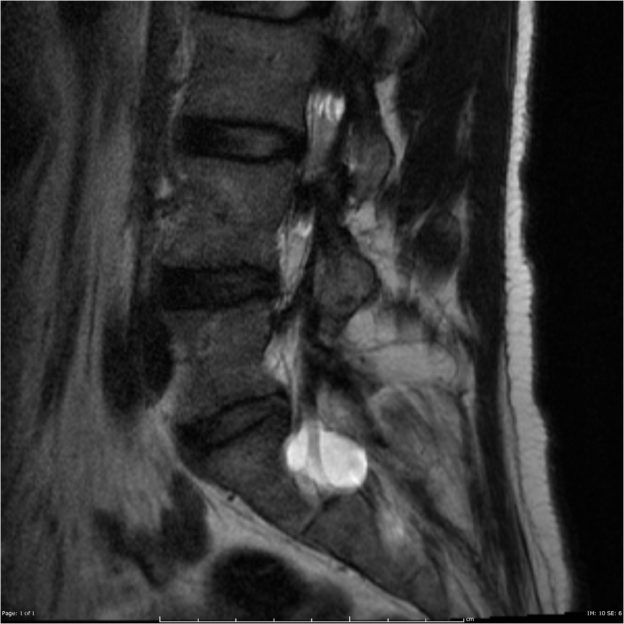

Halk arasında sinir kistleri de denen, yani bel ağrısı şikayeti olan bir insanın belinden çekilen MR(manyetik rezonans) görüntülerinde tesadüfen karşımıza çıkan belde kist görüntüsü; aslında tıbbi adıyla “Tarlov kisti”dir. Bunlar sinirlerin hemen çevresinde yer alırlar.

Hastanın teşhisi MR ile konulabilmektedir.